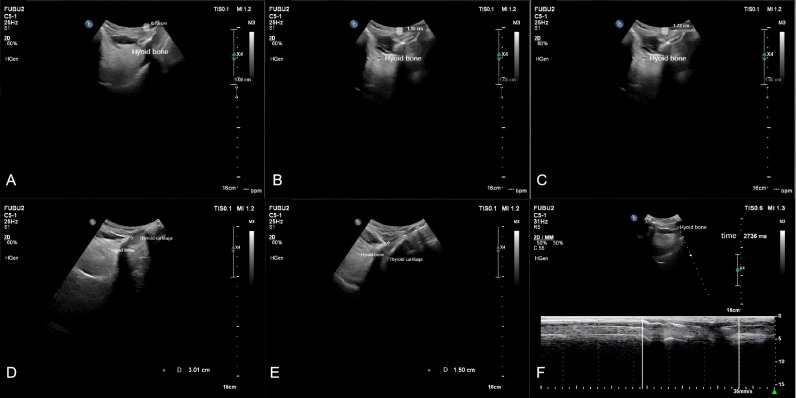

Methods: This study included 46 stroke patients with pharyngeal dysphagia, diagnosed via videofluoroscopic swallowing study (VFSS), and treated at the Department of Rehabilitation Medicine, Affiliated Brain Hospital of Nanjing Medical University (June 2020-August 2024). Swallowing function was assessed using seven pharyngeal phase parameters from the Videofluoroscopic Dysphagia Scale (VDS) at baseline and post-rehabilitation. Patients were stratified into favorable (n = 26) and unfavorable (n = 20) prognosis groups based on post-treatment VDS and Functional Oral Intake Scale (FOIS) scores. Submental B/M-mode ultrasonography quantified hyoid bone displacement parameters pre- and post-rehabilitation, including maximum displacement, anterior displacement, superior displacement, total movement duration, and hyoid-thyroid cartilage approximation ratio (ASR).

Result: No significant differences were observed between groups in baseline characteristics. Post-treatment, the favorable group showed significantly lower Rosenbek scores (p = 0.000), reduced VDS scores (p = 0.000), and decreased feeding tube dependency (p = 0.000). Post-treatment, the favorable group exhibited greater anterior displacement (p = 0.011), higher ASR (p = 0.000), and shorter total movement duration (p = 0.005). Logistic regression identified hyoid anterior displacement (odds ratio (OR) = 9.539, p = 0.011) and ASR (OR = 14.238, p = 0.001) as independent prognostic predictors. ROC curve analysis indicated that hyoid anterior displacement (area under the curve (AUC) = 0.720) and ASR (AUC = 0.816) were significant discriminators of favorable outcomes, with optimal cutoff values of 0.865 cm (92.3% sensitivity, 50.0% specificity) and 31.5% (84.6% sensitivity, 65.0% specificity), respectively. The combined model further improved predictive accuracy (AUC = 0.854, 84.6% sensitivity, 85.0% specificity).